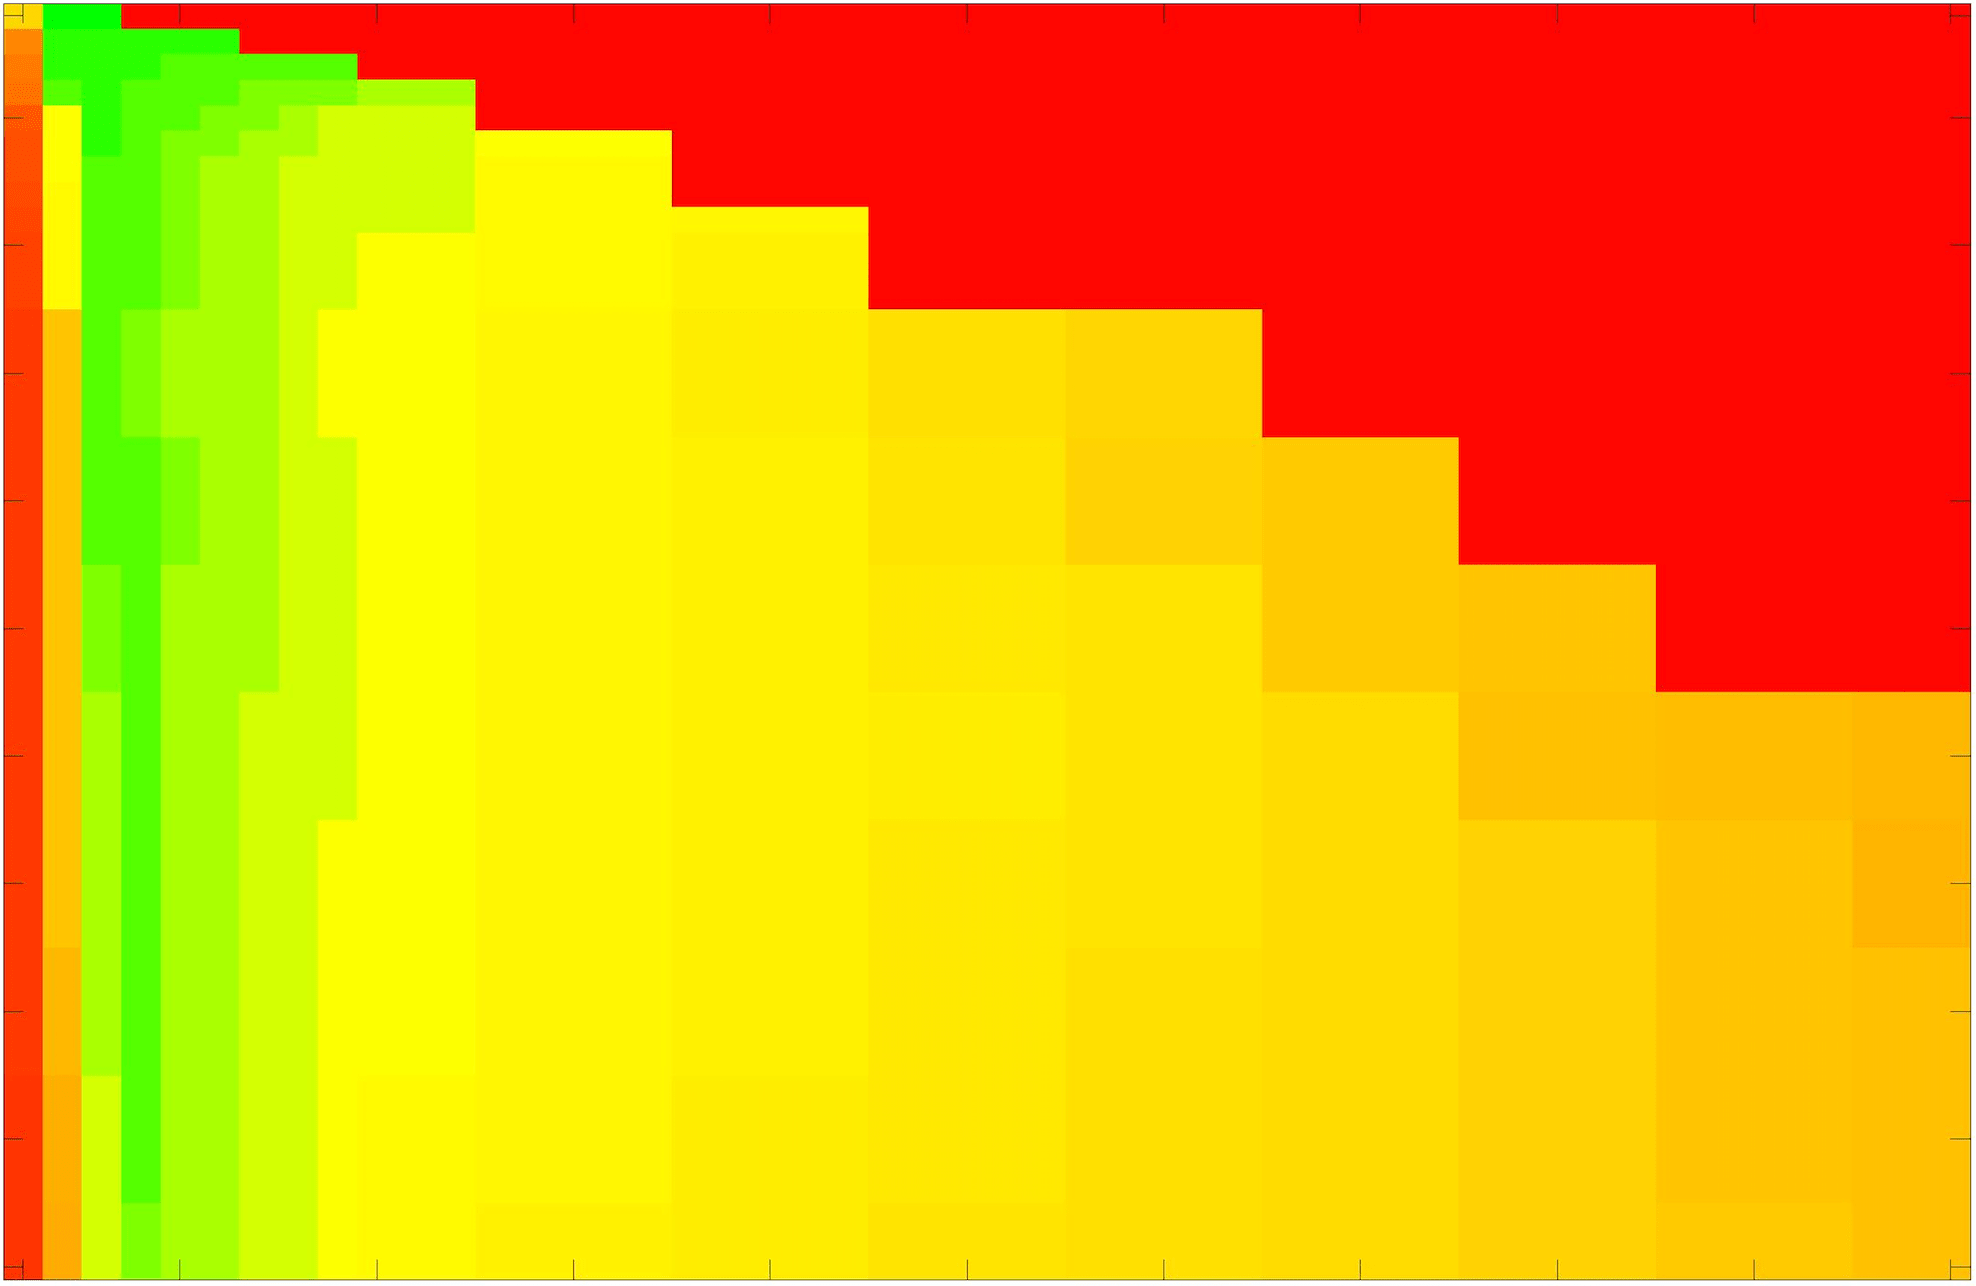

where refers to the number of points in the enclosed region. This takes values in the range , with higher TC values indicating a more accurate segmentation. In the following we will represent accuracy visually from red () to green (), with the intermediate scaling of colours used shown in Fig. 8. This will be particularly relevant in §7.2.

The TC values for the parameter sets are presented as heatmaps in Figs. 11–13. A heatmap is a convenient way to display accuracy results for hundreds of tests concisely. In Fig. 9 we give an example heatmap with the same axes used for those in Figs. 11–13. For each of the combinations of parameter values we give the TC value of the segmentation result and represent it by the appropriate colour. The corresponding colour scale is shown in Fig. 8. Qualitatively, the more green areas of the heatmap the more accurate the model is for a wider set of parameters. Example results for Test Image 5 when varying (with ) for the proposed model are given in Fig. 10. Here it can be seen what each accuracy result corresponds to visually.

Note. The axes have been removed from the heatmaps in Figs. 11–13 for presentational clarity. However, to be explicit, the axes used in all heatmaps are the same as those in Fig. 9.

Synthetic Images. These results are presented in Fig. 11. For Test Images 1–2 we see poor parameter robustness from all competing models, except for GAV which performs reasonably well. However, the proposed model has minimal parameter sensitivity for these images, with good results achieved for almost every combination of values tested. For Test Image 3 all models have a reasonable parameter range (except for RSF), however the proposed model gives better quality results for a wider parameter range. The other models achieve reasonable results here as the foreground intensity of the ground truth is greater than the background , whereas for Test Images 1–2 they are equal . These results highlight the key advantage of the proposed model.

Real Images. In Fig 12 we present results for Test Images 4–6. Here, the proposed model performs in a similar way to its competitors because these images are more typical selective segmentation problems in the sense that there is a clear distinction between the foreground and background intensities. In particular, the values in each case are: Test Image 4 , Test Image 5 , and Test Image 6 . It can be seen that the proposed model is competitive compared to previous approaches. The performance is quite poor for Test Image 5, but is arguably still the best for this challenging case. In Fig. 13 we present results for Test Images 7–9. Here the proposed model outperforms previous approaches significantly for each image. This is mainly due to the type of image considered. Specifically, the true intensities are: Test Image 7 , Test Image 8 , and Test Image 9 . The proposed model is capable of achieving results where , with other models failing completely in these cases.